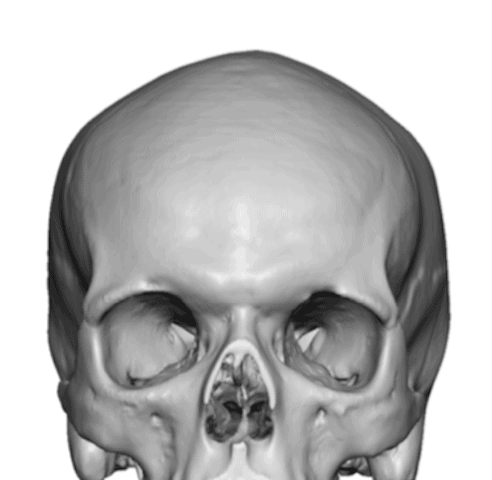

Patient 28

Desire for rounder shape to the top of the head from a congenital parasagittal deficiency skull shape.

Custom skull implant designed to fill in the parasagittal deficiencies.

Desire for rounder shape to the top of the head from a congenital parasagittal deficiency skull shape.

Custom skull implant designed to fill in the parasagittal deficiencies.